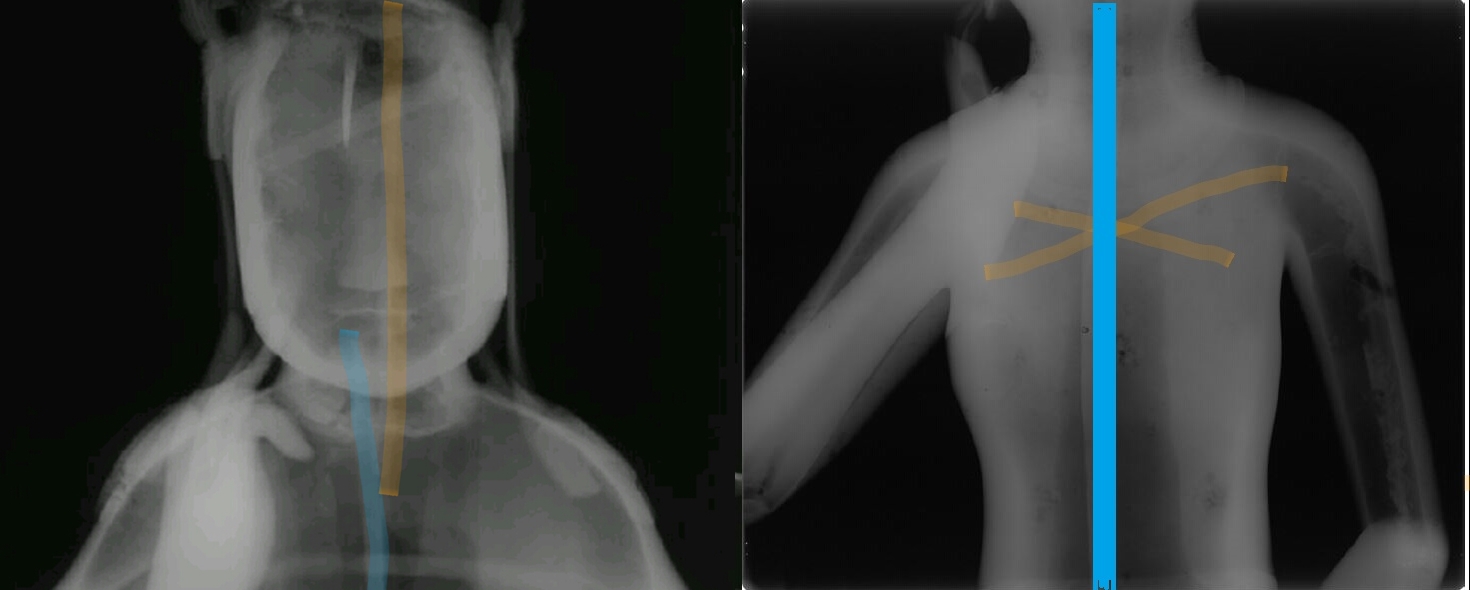

감마선 촬영 결과 78호의 경우 등 부위, 즉 목걸이와 늘어진 U자형 천의(보살 등이 입는 얇은 옷) 사이에 반타원형 동판을 따로 붙인 흔적을 확인했다. 주조할 때 생긴 구멍을 동판으로 붙여 수리한 흔적이었다. 지금까지 육안으로 관찰되지 않았던 수리흔적이 첨단과학을 동원하고 나서야 겨우 드러난 것이다.

그런데 78호를 감마선으로 분석해봤더니 철심틀이 분리되어 있었다.

이것은 점토(내형토)로 맨처음 형상을 만들 때 몸체와 머리 부분을 각각 따로 만들어 붙였다는 뜻이다. 왼발의 연화좌(불상이 앉는 자리) 역시 따로 제작해서 붙였다.

이렇게 별도로 만들어 붙였기 때문에 미세한 균열이 생겼고, 그 사이에 청동 쇳물이 흘러들어가 거스러미(까칠까칠한 부분)이 생겼다. 하지만 이 또한 육안이나 X선 촬영으로는 잡아낼 수 없는 흠결이었다.

또 비파괴방법 등으로 성분을 분석해보니 78호의 본체는 주석이 5% 정도 들어간 ‘구리-주석’ 합금이었다. 그런데 뒷면에 덧댄 동판과 수리흔적이 보이는 양 옆구리 부분에서는 주석 대신 납이 3% 정도 들어있는 구리-납 합금 성분이 보였다. 또 본체와 떨어져 있는 천의 자락과 보관 장식 중 일부도 구리-납의 합금이었다. 무슨 뜻일까. 주조가 한번이 아니라 몇번에 걸쳐 이뤄졌다는 것을 의미한다.

즉 처음 주조(구리-주석 합금) 때 쇳물이 제대로 흘러 들어가지 않아서 결함이 발생한 부분도 있었을 것이다. 또한 본체와는 떨어져있는 천의 부분은 처음부터 쇳물이 흘러 들어가지 못했을 것이다. 이런 부분을 ‘구리-납’의 합금 쇳물로 다시 주조했거나 혹은 별도의 납땜질 수리로 감쪽같이 마무리 한 것이다. 물론 이 역시 육안 또는 X선 촬영으로는 볼 수 없었던 흠결이었다.

정리하자면 78호 제작 때 등의 한가운데와 허리, 의자 뒤쪽의 윗부분, 몸체의 정수리 부분, 그리고 몸체와 떨어져있는 천의와 보발, 보관의 끝부분 등은 쇳물이 제대로 흘러가지 않아 결함이 생겼다는 뜻이다. 당시 분석에 참여한 민병찬 관장은 “78호의 이런 결함들을 구리 순도가 높은 구리-납 합금의 쇳물로 수리했다”면서 “일부는 결함 부분에 직접 쇳물을 부어 처리했거나 일부는 별도로 주조해서 붙였을 것”이라고 해석했다.

민병찬 관장은 “78호 반가사유상의 두께가 너무 얇았기 때문”이라고 풀이한다. 그랬다. 분석결과 78호의 몸체 두께는 평균 4㎜에 불과했다(83호는 평균 10㎜). 6세기 중후반 78호를 제작한 장인은 내형토와 외형토의 사이를 메운 밀납 공간을 최대한 얇게 둠으로써 흘러들어가는 쇳물의 두께를 최소화 했다.